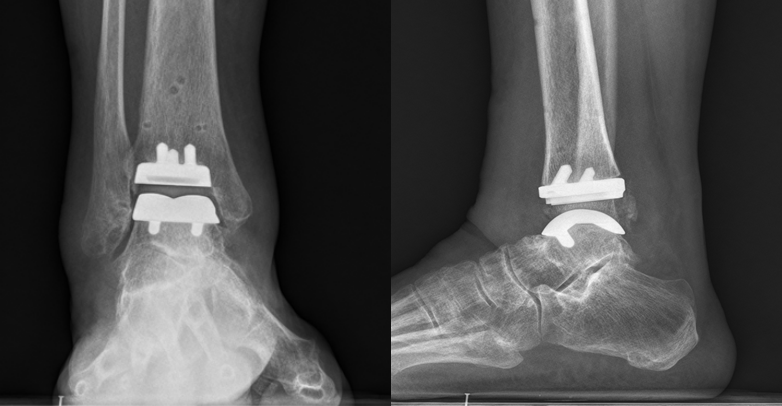

术后复查右踝关节片

手术在我院外聘专家曾参军教授的现场指导下,由万富贵主任医师、何洪武副主任医师共同协作完成。术中团队操作精细,配合默契,手术过程顺利。邓阿姨术后恢复良好,现右踝关节活动正常,已恢复正常行走功能。

万富贵主任介绍,踝关节炎的治疗方式分为药物治疗与手术治疗两大类。一旦踝关节骨关节炎进展为终末期关节炎,传统治疗手段往往难以达到理想疗效。全踝关节置换术是治疗终末期踝关节炎(如创伤性、类风湿性或原发性骨关节炎)的重要外科手段。相比传统的踝关节融合术,其优势在于消除疼痛的同时能保留关节活动功能,并减少邻近关节的退变风险,为患者带来更优的生活质量。